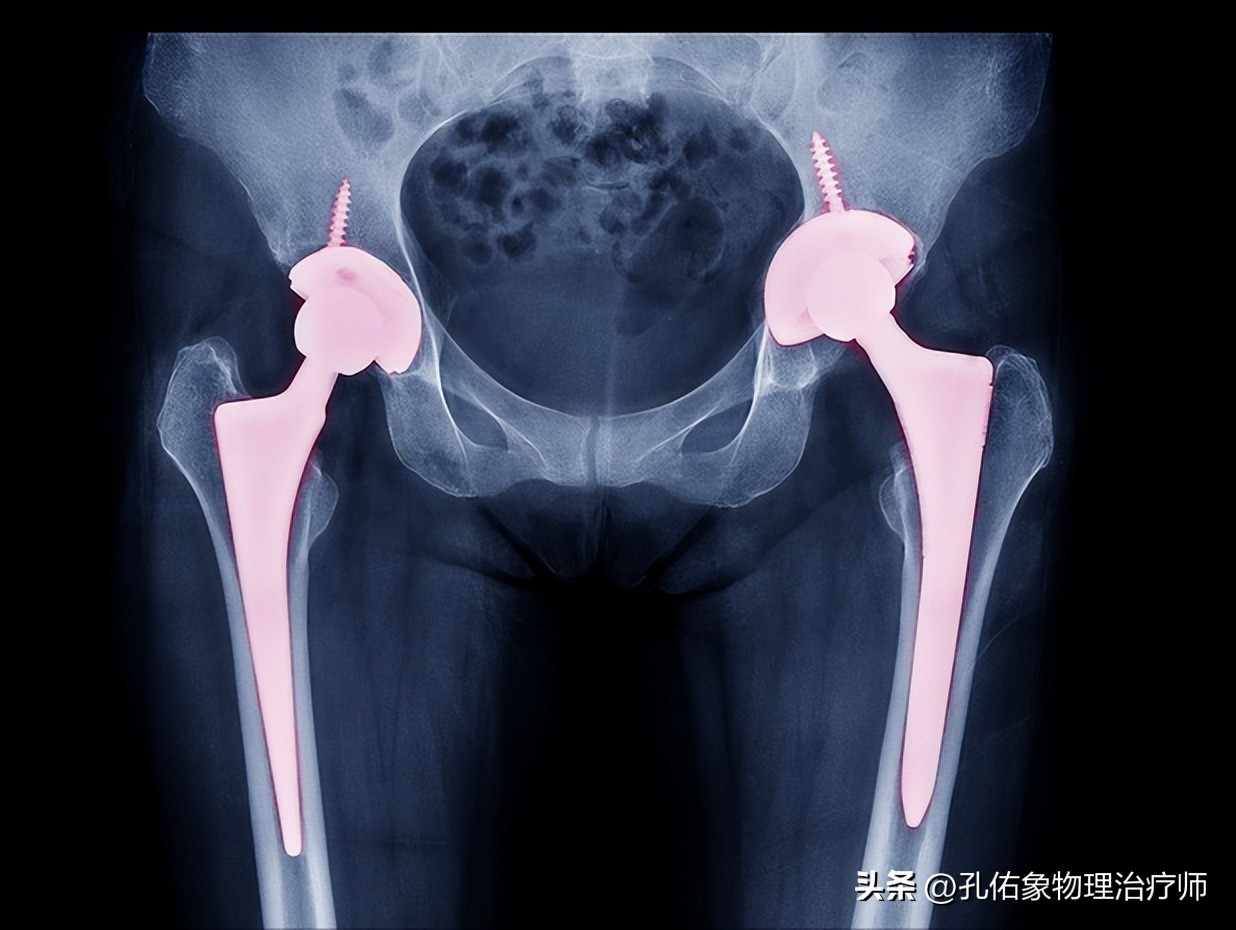

医生告知她,需要做手术了,并且要置换关节,没法再保守继续使用了;罗女士纳闷了,年纪轻轻的,怎么一个胯部疼痛就坏死了呢?

1.股骨头坏死

之所以,把这种疾病介绍在最前面,是因为它是一种比较严重的关节病,希望大家引起重视,不要忽略它。

如上图所示,第一张是正常的,在关节的骨头表面有血管支配,倘若骨头表面的血液供应受到某种原因影响,骨头表面缺血,部分骨细胞就会凋亡,逐渐出现骨坏死,发生骨头塌陷、形变而没法完成它的承重及活动功能。